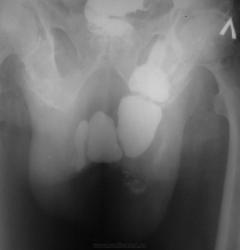

Она не в бедре, там огромный грыжевой мешок с кишками, к сожалению сохранился только этот обзорный снимок. На первое мая решил разобраться в архивах на компьютере...

Да, такую "бедренную грыжу" видеть не приходилось, да и сейчас не сильно верится..., по всей видимости живот в виде "фартука" наслаивается...

Не верю! Автор сами знаете кто... Почему подвздошная кишка уходит на левое колено?

Могу предположить наличие огромной грыжи белой линии живота, в которую вывалился "ливер" и она болтается спереди в виде "фартука".

На момент исследования болен около 4 лет, операции боялся по этому "носил" до последнего.

По ссылке тоже просмотрел картинки. Похожа там 04 и 16. Но не так, не так.